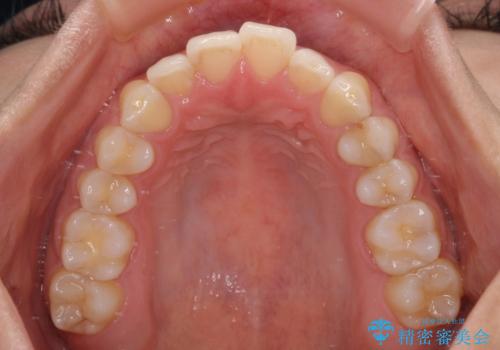

前歯の重なりをインビザライン・モデレートで矯正治療

- 上下前歯の重なりを気にして来院された患者様です。

安価なインビザラインパッケージを用いての治療を希望されており、デコボコの程度が中等度であったため、インビザライン・モデレートを用いて矯正治療を行うこととしました。

インビザライン・モデレートは、製作できるアライナーの枚数に制限があるため、移動可能な量に限りがあるものの、インビザライン・ライトよりも枚数が多いため、幅広い症例に対応可能です。